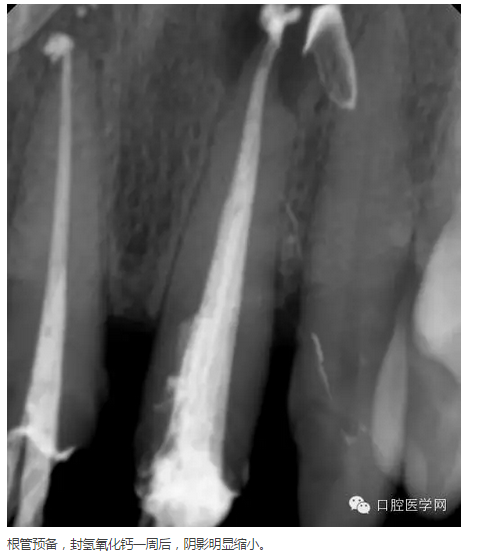

治療方案:建議拆除牙冠,21行根管治療,樁核、全冠修復(fù)